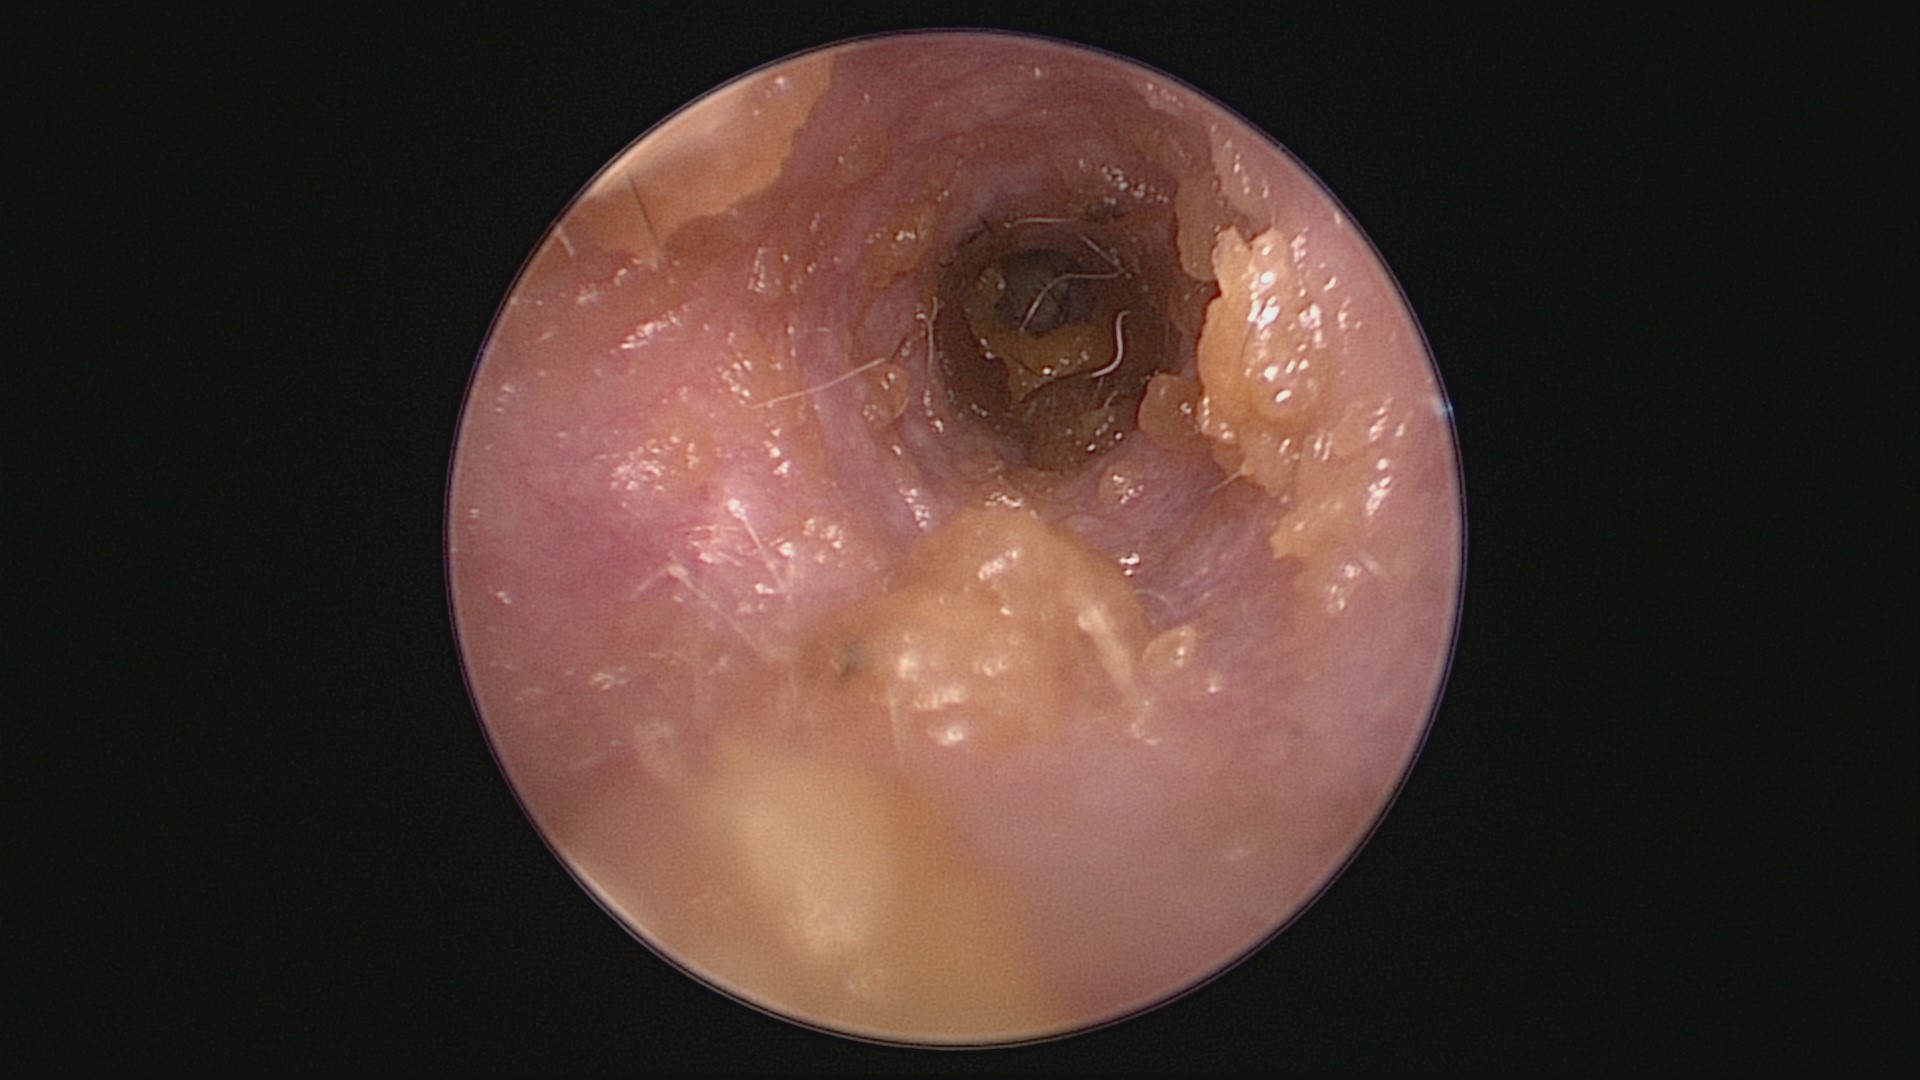

Erythème du méat acoustique externe chez un labrador atopique.

La dermatite atopique peut engendrer une inflammation auriculaire initialement asymptomatique, en particulier chez les jeunes animaux. Il est donc important d'examiner systématiquement les conduits auditifs des chiens atopiques afin de détecter un érythème du méat acoustique externe, une inflammation proximale ou une hyperplasie débutante des glandes cérumineuses. L'identification de ces anomalies doit être considérée comme pathologique.